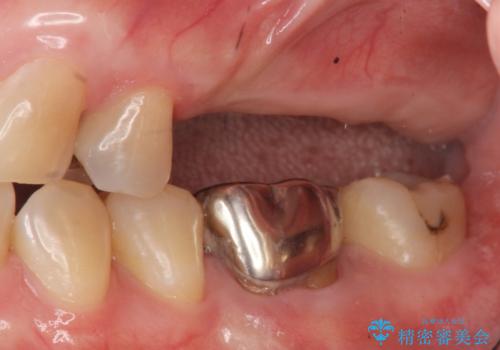

- 110万円(インプラント×2・チタンカスタムアバットメント×2・ジルコニアクラウン×3・仮歯×3)費用は治療当時の料金となります

しっかりと噛めるようになったことで、また食事を楽しんでいただくことができるようになりました。